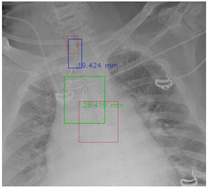

Figure 7 and Figure 8 demonstrate the effect of post-processing. The red bboxes and points in these figures are the GT ETT/bifurcation bboxes and the position of GT ETT tip/Carina, respectively. The green polygon is the GT mask of the ETT and the bifurcation. The blue bbox and point are the predicted ETT bbox and ETT tip, respectively. The yellow bbox and point are the predicted bifurcation and Carina, respectively. Specifically, without the post-process, the model might leave more than one predicted ETT tip/Carina, such as where the red arrow points in Figure 7a. However, with the post-process, the extra points would be removed as shown in Figure 7b. Besides, with the refinement process in the post-process, the feature point of ETT tip/Carina could be further refined as shown in Figure 8. Concretely, the object error of Carina was corrected from 8.469 mm to 1.319 mm.

Figure 7.

Ensuring at most one ETT tip/Carina left. (a) Without post-process. (b) With post-process.

Figure 8.

Refining the feature point of ETT tip/Cairna by the bbox of ETT/Bifurcation. (a) Without post-process. (b) With post-process.